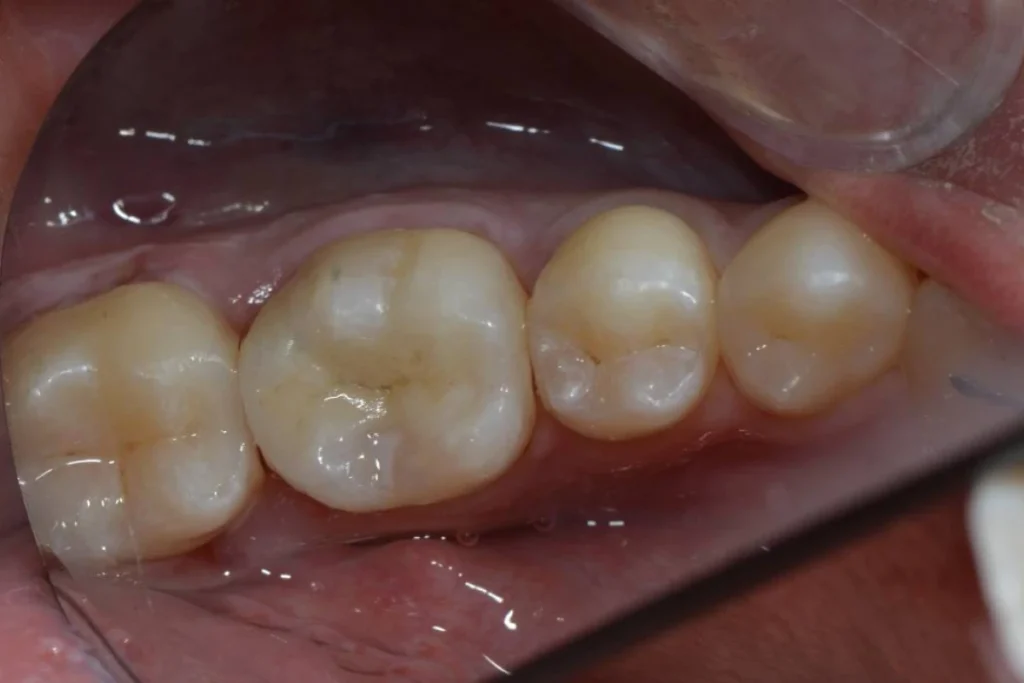

Restauration d’une dent dévitalisée avec un inlay / onlay en céramique